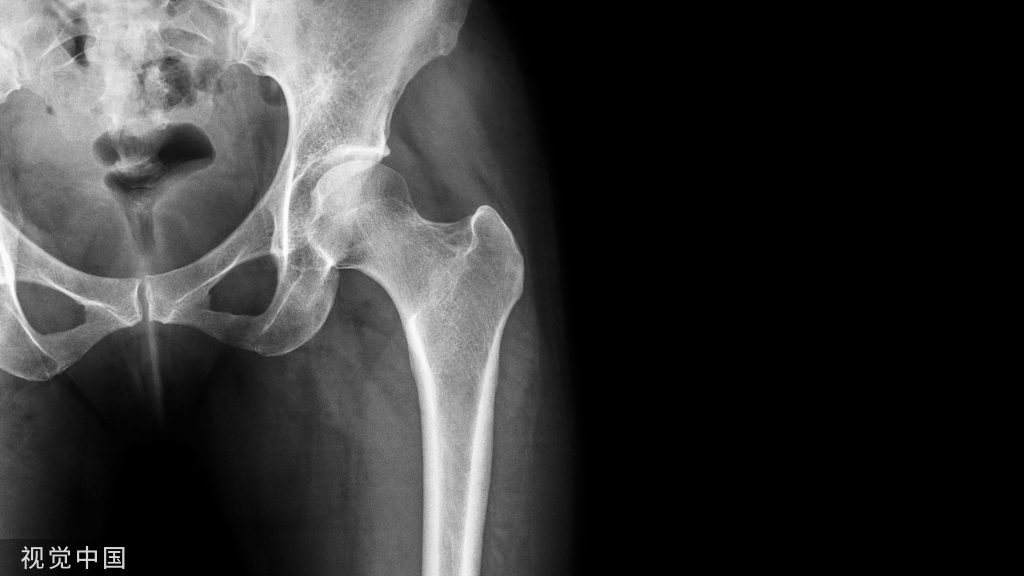

看看这些失败的case,肱骨远端不简单!